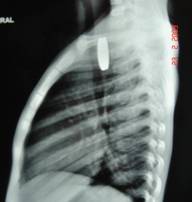

Acute Scrotum (Right scrotal Abscess)

Torsion of Left Undescended Testis (Pre operative and Operative Photo)

Acute Scrotum

Torsion Testis (Pre and Per operative photo)